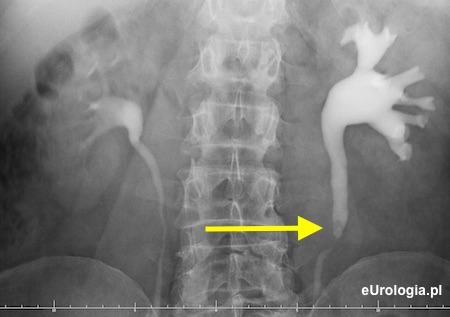

Urografia - kamica górnego odcinka lewego moczowodu

Cień wapienny w rzucie lewego moczowodu na wysokości przestrzeni międzykręgowej L3/L4 po stronie lewej

Wodonerczowato poszerzony UKM lewej nerki i lewy moczowód aż do opisywanego na zdjęciu cienia - złóg w lewym moczowodzie.

Złóg o wymiarach 10x7 milimetrów w górnym odcinku lewego moczowodu